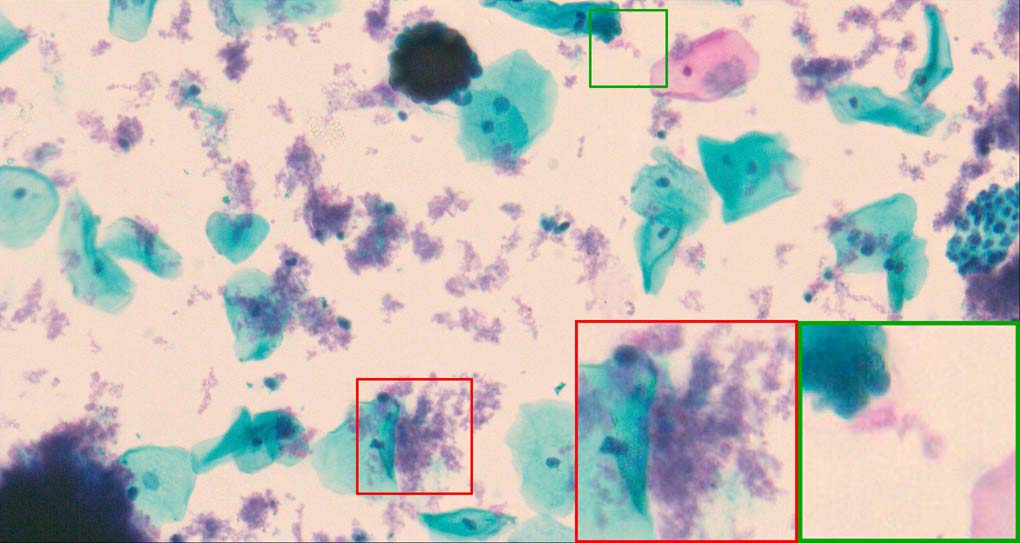

A good image fusion method should contain the following properties. First, it preserves both the details of small size objects and the integrity information of large size objects in the fused image, even in the case of the size of the interested objects varying largely in the image. For example, the cervical cell images from the microscope contain both small size isolated cells and large size agglomerates, which are both useful for cervical cytology [5]. Second, it should be efficient enough to handle large-scale data. For instance, it needs to process thousands of fields of view (FoV) in an acceptable time for the whole slide scanning in digital cytopathology [6], which requires to fuse a series of high resolution images captured at each FoV in a very efficient way. Third, it does not produce obvious artifacts. Despite being studied extensively, to our best knowledge, existing fusion methods may not meet these requirements simultaneously.

To demonstrate the effectiveness and efficiency of the proposed image fusion method , we conduct a set of comparative experiments on three image datasets. The first is composed by 8 pairs of multi-modal medical images and the second one contains 15 pairs of multi-focus gray or color natural images. These two datasets are often used in many related papers and some examples are shown in Figure 3(a) and Figure 3(b). The third one is a new multi-focus cervical cell image dataset collected by ourselves, which consists of 15 groups of color images and each group contains a series of multi-focus cervix cell images with size of or , etc. Some source examples are shown in Figure 3(c). Our source code implemented in C++ along with the new multi-focus cervical cell image dataset is available online.

Figure 9, Figure 10 and Figure 11 show the comparative fused results of the multi-focus cell images shown in Figure 3(c). For clarity, we also present a closeup view in the right-bottom of each sub-picture in Figure 9 and Figure 10. As shown in the close-up views of Figure 9, the fused images based on DSIFT, IM, MWGF and BF methods are extremely blurred in the boundary and fail to keep the details of cell nucleus. Furthermore, the DTCWT and NSCT based methods produce halo artifacts in the fused images, while GFF and CNN based methods fail to preserve the small cell nucleus. LP-SR based method nearly works fine which keeps the most of the details of the small size cells, but the integrity of the clustered large size cells is damaged. Fortunately, in our proposed method, the integrity of the clustered large size cells is preserved and most of the isolated small size cells are maintained from the original images, which demonstrates the best visual quality.

Similarly, as shown in the close-up views of Figure 10, the fused images from DSIFT, IM, MWGF and BF are blurred and lose some nucleus details, while the results from DTCWT, GFF, CNN and NSCT produce halo artifacts. LP-SR based method can keep details well but also produces halo artifacts and other noise. Our method can preserve the focused areas of different source images well without introducing any artifacts. For the example illustrated in Figure 11, the fused images generated by DSIFT, DTCWT, IM and NSCT all fail to preserve the focused areas of different source images and result in extremely blurred images. The GFF, CNN, MWGF and BF based method introduces a lot of color distortion of the nucleus regions and the obvious halo artifact. The result of LP-SR based method is close to the one of our method but introduces some odd color distortion. Again, our method produces fused image which can preserve the focused areas of different source images well without introducing any artifacts.